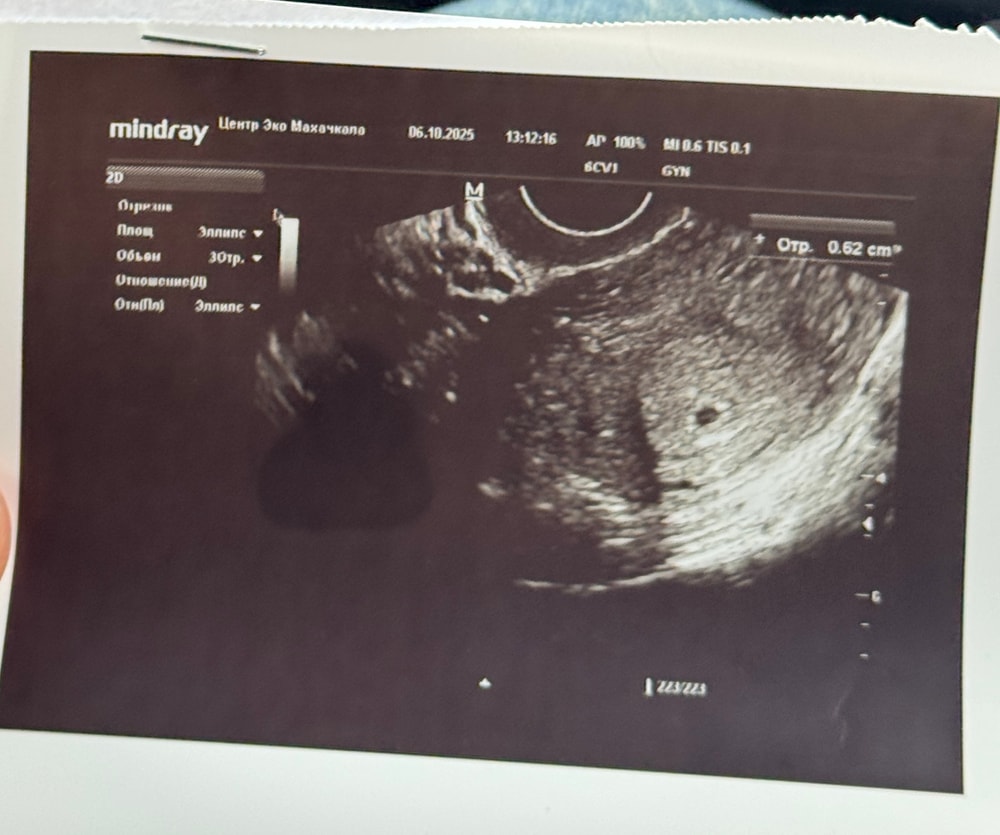

0,62 cm это размер ПЯ?